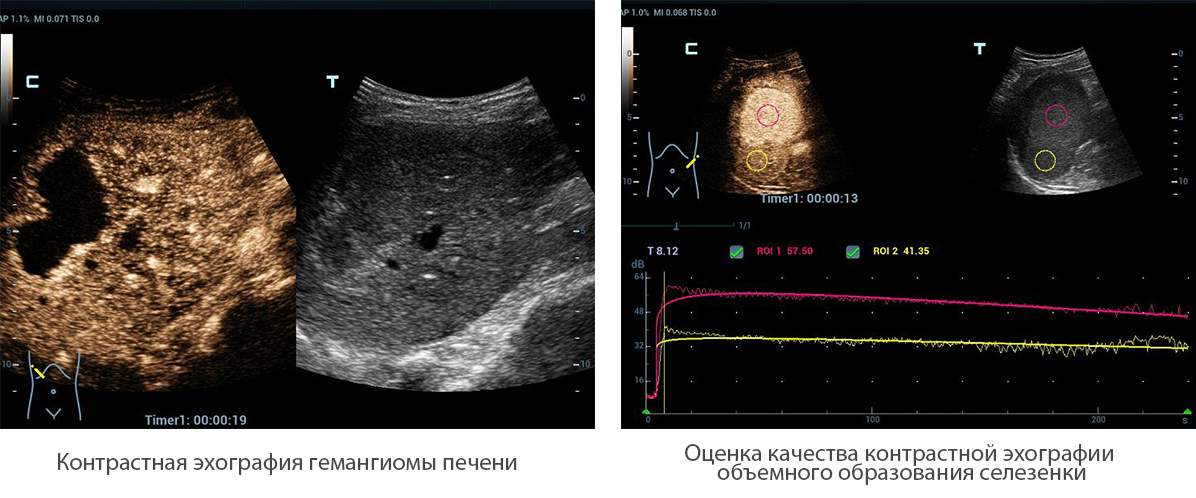

–Ъ–Њ–љ—В—А–∞—Б—В–љ–∞—П –≤–Є–Ј—Г–∞–ї–Є–Ј–∞—Ж–Є—П UWN (–љ–µ–ї–Є–љ–µ–є–љ–∞—П –≤–Є–Ј—Г–∞–ї–Є–Ј–∞—Ж–Є—П –≤ —Г–ї—М—В—А–∞—И–Є—А–Њ–Ї–Њ–Љ –і–Є–∞–њ–∞–Ј–Њ–љ–µ)

UWN+?(–љ–µ–ї–Є–љ–µ–є–љ–∞—П –≤–Є–Ј—Г–∞–ї–Є–Ј–∞—Ж–Є—П –≤ —Г–ї—М—В—А–∞—И–Є—А–Њ–Ї–Њ–Љ –і–Є–∞–њ–∞–Ј–Њ–љ–µ) –і–ї—П –Ї–Њ–љ—В—А–∞—Б—В–љ–Њ–є —Н—Е–Њ–≥—А–∞—Д–Є–Є –њ–Њ–Ј–≤–Њ–ї—П–µ—В —Б–Є—Б—В–µ–Љ–µ Resona 6 –Њ–±–љ–∞—А—Г–ґ–Є–≤–∞—В—М –Є –Є—Б–њ–Њ–ї—М–Ј–Њ–≤–∞—В—М –Ї–∞–Ї –≤—В–Њ—А—Л–µ –≥–∞—А–Љ–Њ–љ–Є–Ї–Є, —В–∞–Ї –Є –љ–µ–ї–Є–љ–µ–є–љ—Л–µ –њ–µ—А–≤–Є—З–љ—Л–µ —Б–Є–≥–љ–∞–ї—Л. –Ґ–µ—Е–љ–Њ–ї–Њ–≥–Є—П –њ–Њ–Ј–≤–Њ–ї—П–µ—В —Б–Њ–Ј–і–∞–≤–∞—В—М –Є–Ј–Њ–±—А–∞–ґ–µ–љ–Є—П –Ї–Њ–љ—В—А–∞—Б—В–љ–Њ–є —Н—Е–Њ–≥—А–∞—Д–Є–Є –±–Њ–ї–µ–µ –≤—Л—Б–Њ–Ї–Њ–≥–Њ –Ї–∞—З–µ—Б—В–≤–∞ —Б –±–Њ–ї—М—И–µ–є —З—Г–≤—Б—В–≤–Є—В–µ–ї—М–љ–Њ—Б—В—М—О –Ї–Њ –≤—В–Њ—А–Њ—Б—В–µ–њ–µ–љ–љ—Л–Љ —Б–Є–≥–љ–∞–ї–∞–Љ, –±–Њ–ї—М—И–Є–Љ –≤—А–µ–Љ–µ–љ–µ–Љ –і–µ–є—Б—В–≤–Є—П –∞–Ї—В–Є–≤–љ–Њ–≥–Њ –≤–µ—Й–µ—Б—В–≤–∞ –Є –±–Њ–ї–µ–µ –љ–Є–Ј–Ї–Є–Љ–Є —В—А–µ–±–Њ–≤–∞–љ–Є—П–Љ–Є –Ї –Є–љ—В–µ—А–≤–∞–ї—Г –Є–Ј–Љ–µ—А–µ–љ–Є—П.